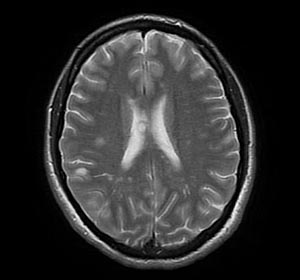

Информация о диссеминированном рассеянном энцефаломиелите